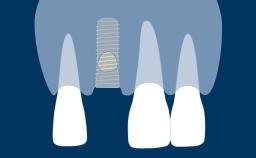

- discuss the following supportive elements and superstructure options for single unsplinted implants: retentive stud attachments, functional single crowns